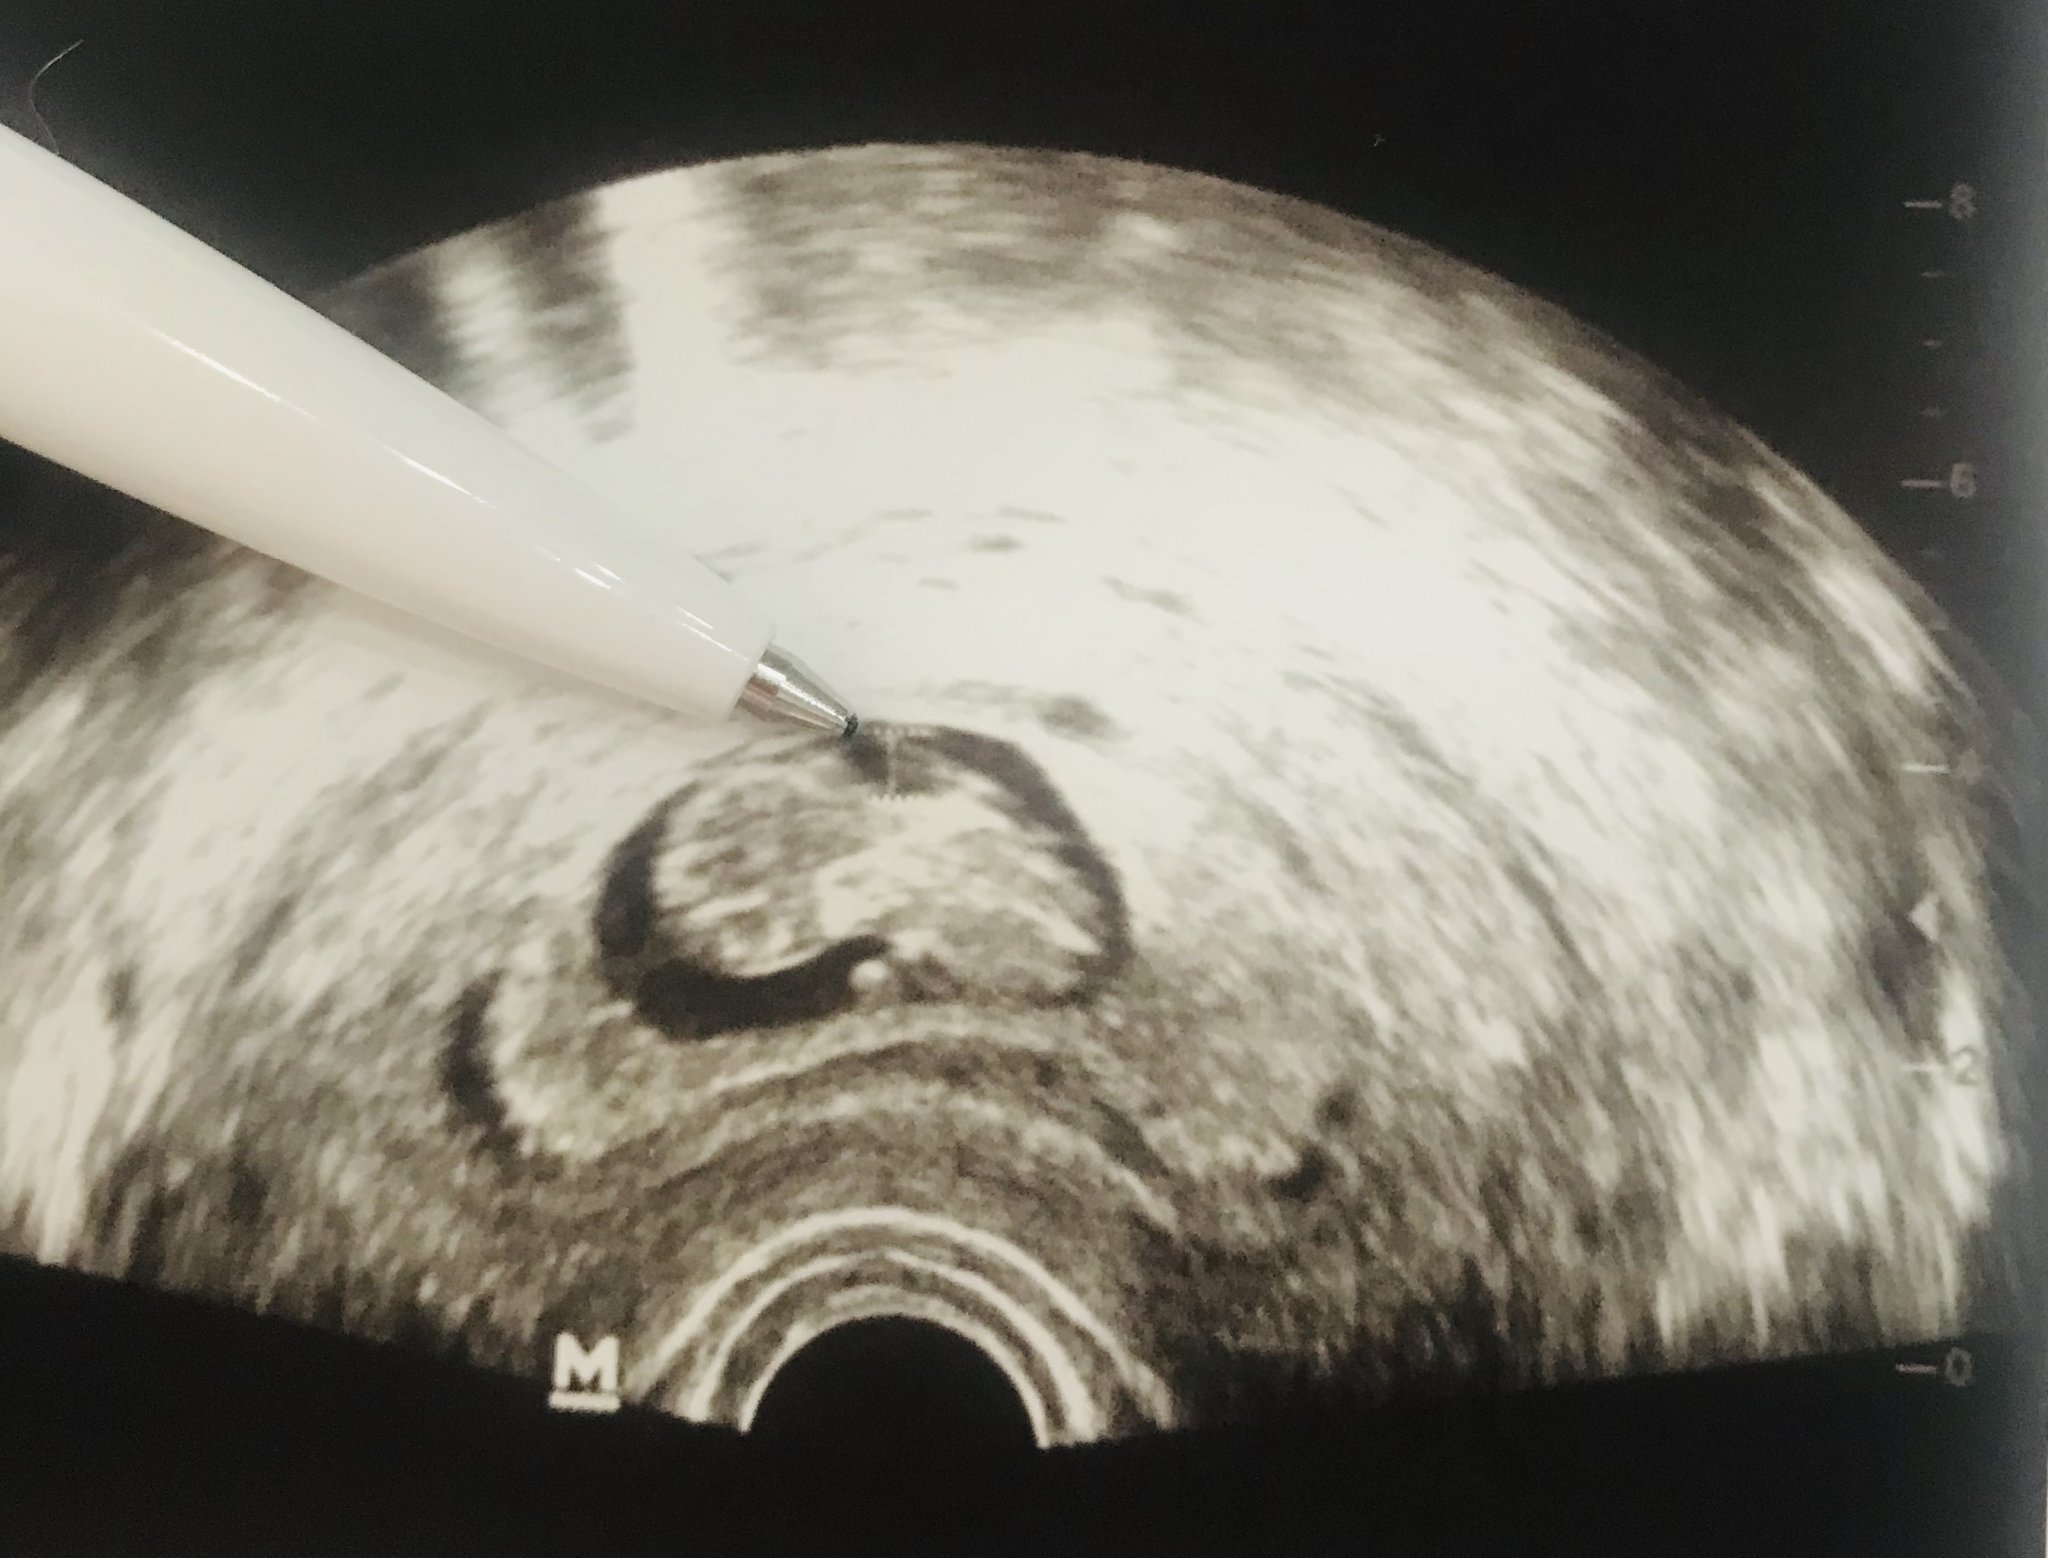

В 10 г.с. Вижда някакво разстояние, място, луфт (нз как да го нарека), но то при синдром било до 2мм, моето е над 4мм.